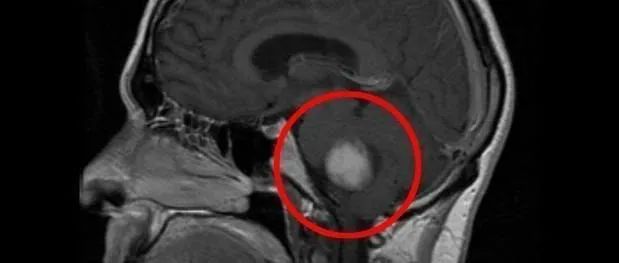

病史简介患者男性,64岁,因“右侧听神经瘤术后面瘫11月”入院。 患者11月前因“右耳听力下降6年余”,行检查发现右侧听神经瘤,排除手术禁忌后,于2021年8月25日行右侧桥脑小脑角病损切除术,术后病理提示:神经鞘瘤。予营养神经对症支持治疗,遗留右侧面瘫,右侧额纹消失,眼睑闭合不全,口唇歪斜, 现患者为正畸求医至至浙大二院神经外科二病区陈景森医生团队,门诊拟“面神经损伤”收住入院。 ...

来源:中华神经外科杂志, 2021,37(5) : 433-438.一、概述随着诊疗技术的不断提升,听神经瘤手术关注的重点已从降低手术病死率转向提高脑神经功能的保留率[1,2,3,4]。因大多数患者的耳蜗神经功能在术前已存在不同程度的缺失,故听力的保留一般比较困难;而面神经功能在术前很少异常,肿瘤切除后有望保留面神经功能。面神经功能的保留不仅依赖于医生娴熟的手术操作技巧、与神经电生理监测团队的良好合作...